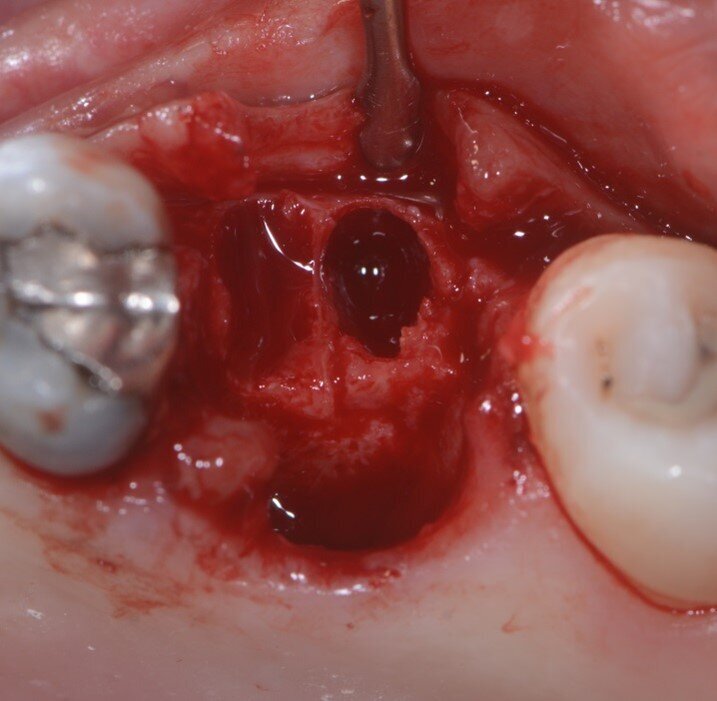

È stata eseguita una CBCT preoperatoria (Figg. 2a, 2b). La paziente, una donna di 52 anni in buona salute, ha iniziato la terapia antibiotica il giorno prima dell’estrazione con 2 gr. Amoxicillina e Acido Clavulanico. Dopo l’anestesia locale, è stata eseguita un’estrazione atraumatica cercando di non danneggiare le corticali ossee. L’alveolo è stato accuratamente pulito e risciacquato con acqua ossigenata e clorexidina 0,2% (Fig. 3). È stata praticata un’incisione intrasulculare sull’aspetto vestibolare dell’alveolo estrattivo, estendendosi al centro dei denti adiacenti. Un lembo a tutto spessore è stato sollevato ed il periostio staccato con micro-scollatori ha permesso di creare una busta per la lamina corticale (Fig. 4). La lamina corticale soft da 0,5 mm è stata prima idratata per cinque minuti in soluzione sterile e poi tagliata nella forma desiderata, tra 8 e 10 mm di altezza e con un’estensione che copre i margini mesiali e distali dell’alveolo estrattivo. La lamina corticale può essere facilmente inserita nel sito ed eventualmente ritagliata fino ad ottenerne un perfetto adattamento. I bordi devono essere rifiniti con angoli arrotondati per ridurre il rischio di perforazione e/o deiescenze sul versante vestibolare. La colla di fibrina umana (Tisseel, Baxter) è stata diluita al 10% mediante 0,9 ml di acqua bidistillata. Sulla lamina corticale sono state applicate due o tre gocce di colla, dopo di che la lamina è stata poi schiacciata con una gentile pressione digitale per adattarsi alla posizione predefinita (Fig. 5). Il lato palatale dell’alveolo è stato invece lasciato guarire per prima intenzione. Una spugna di collagene (Condress, Smith & Nephew) è stata inserita all’interno dell’alveolo per stabilizzare il coagulo ed è stata posizionata una sutura incrociata (4-0 punti di sutura in ptfe) per mantenere la spugna in posizione, le papille sono state invece suturate con due suture a fionda7 (Fig. 6). Quattro mesi dopo l’estrazione, prima di inserire l’impianto, è stata eseguita una CBCT post-operatoria per valutare la guarigione del sito operato.

Fig. 3 -Alveolo post estrattivo.